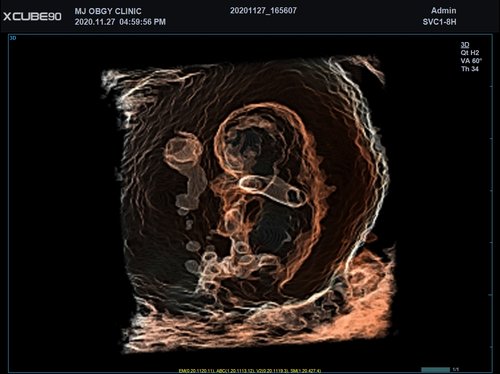

Mit dem X-CUBE 90 beginnt ALPINION eine neue Generation an Farbdopplersystemen, die X- CUBE Serie. Mit Bildverarbeitungstechnologien eines Premiumsystems und neuen Breitband- Schallköpfen mit X + Crystal Signature™ Technologie wartet das neue X-CUBE 90 auf.

X + Architecture

Die X + Architecture ist eine erstklassige Imaging-Plattform, die durch die Kombination von X + Crystal Signature™, der Schallkopftechnologie mit hoher Sensitivität und Breitbandigkeit, und X + FIT, ALPINIONs modernste Beamforming- und Datenverarbeitungstechnologiengeschaffen wurde. X + FIT ist eine neue Technologie, die den Schallstrahl scharf fokussiert sendet, ein großes Datenvolumen empfängt und mit hoher Geschwindigkeit verarbeitet. Darüber hinaus nutzt X + Crystal Signature™ Einkristalle und unser eigenes entwickeltes Schallkopfmaterial, um eine hervorragende Brillanz zu erzielen und die Diagnosemöglichkeiten zu erweitern.

• SVC1-8H (1-8 MHz) für Ultraschalluntersuchungen in Bereichen Abdomen, Geburtshilfe, Gynäkologie, Urologie, Pädiatrie, EM